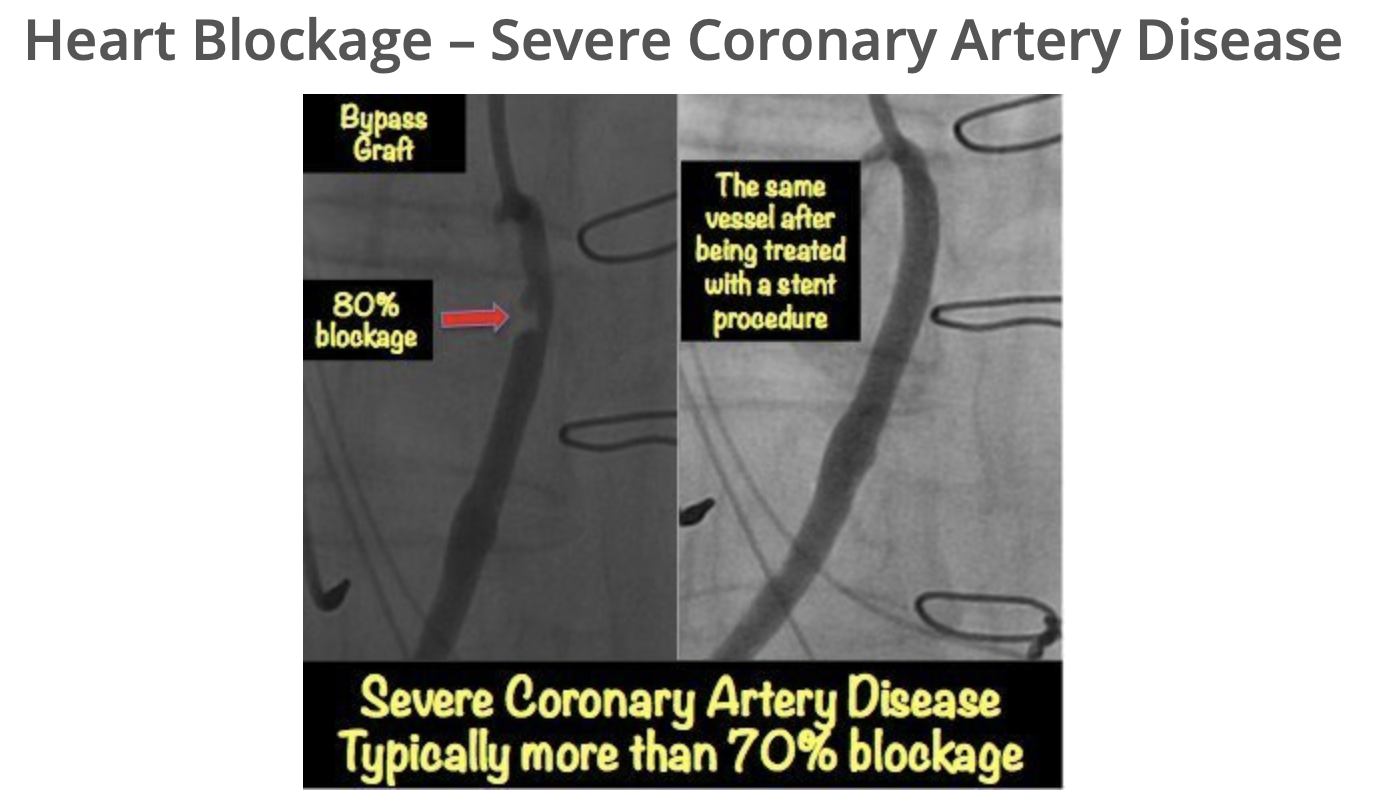

![“ We performed the first coronary angioplasty [at UAB] in 1982, and the technology raced ahead in the years to follow. Particularly important was the development of the stent, a tiny spring ‘like that in your ball-point pen, only a bit larger,’ p](https://images.squarespace-cdn.com/content/v1/522b22f2e4b04879e6b51037/1596998467392-T37YI1NAKLYGVW2T44Z3/Screen+Shot+2020-08-09+at+1.39.09+PM.png)

![“ We performed the first coronary angioplasty [ at UAB] in 1982, and the technology raced ahead in the years to follow. Particularly important was the development of the stent, a tiny spring ‘like that in your ball-point pen, only a bit large](https://images.squarespace-cdn.com/content/v1/522b22f2e4b04879e6b51037/1596755620909-1HRJBE6NLW8ZE6LCKP1P/IMG-7986.jpg)